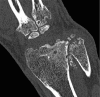

Photon-counting detector (PCD) CT is an emerging technology that has shown tremendous progress in the last decade. Various types of PCD CT systems have been developed to investigate the benefits of this technology, which include reduced electronic noise, increased contrast-to-noise ratio with iodinated contrast material and radiation dose efficiency, reduced beam-hardening and metal artifacts, extremely high spatial resolution (33 line pairs per centimeter), simultaneous multienergy data acquisition, and the ability to image with and differentiate among multiple CT contrast agents. PCD technology is described and compared with conventional CT detector technology. With the use of a whole-body research PCD CT system as an example, PCD technology and its use for in vivo high-spatial-resolution multienergy CT imaging is discussed. The potential clinical applications, diagnostic benefits, and challenges associated with this technology are then discussed, and examples with phantom, animal, and patient studies are provided. ©RSNA, 2019.